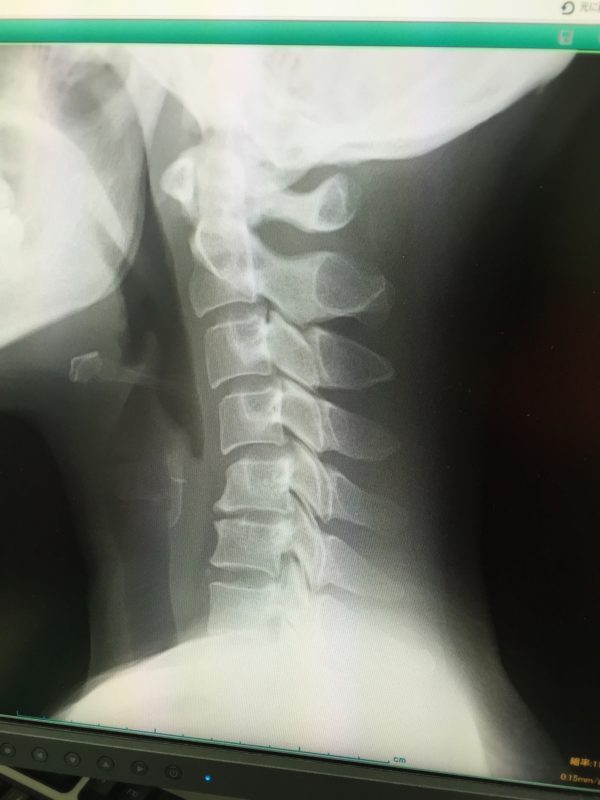

ストレートネックとは、本来ゆるやかなカーブを描いている首の骨(頸椎)が、まっすぐになってしまう状態のことを指します。正式には「頸椎前弯減少」とも呼ばれ、近年、スマートフォンやパソコンの普及により、多くの人がこの状態に悩まされています。

正常な頸椎のカーブとストレートネックの違い

健康な首の骨は、約30〜40度の前弯(前に向かってカーブ)があることで、頭の重さ(約5kg)をバランスよく支えています。しかし、ストレートネックになると、このカーブが失われ、首がまっすぐになり、頭が前方に出た状態になります。

- 正常な首の状態:S字カーブを保ち、首・肩・背中の筋肉に負担が少ない。

- ストレートネックの状態:頭が前に出てしまい、首や肩に過剰な負荷がかかる。